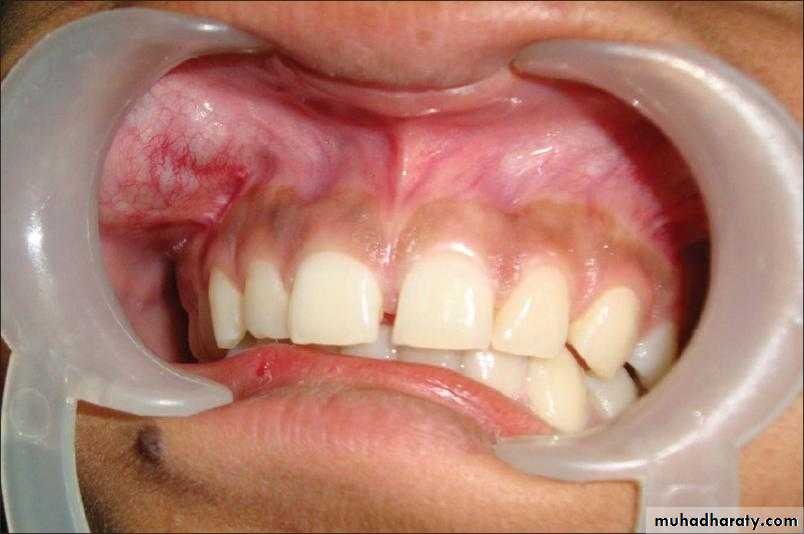

Intraorally, pleomorphic adenomas most often occur on the palate, followed by the upper lip and buccal mucosa.

Rare case of PA on the Buccal mucosa